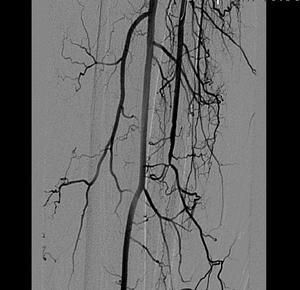

Пациентка К, 1952 г.р. (55 лет).

- Атеросклероз.

- Сахарный диабет.

- Окклюзия артерий левой голени.

- Ишемия левой нижней конечности 4 степени.

- Длительно не заживающая рана левой стопы.